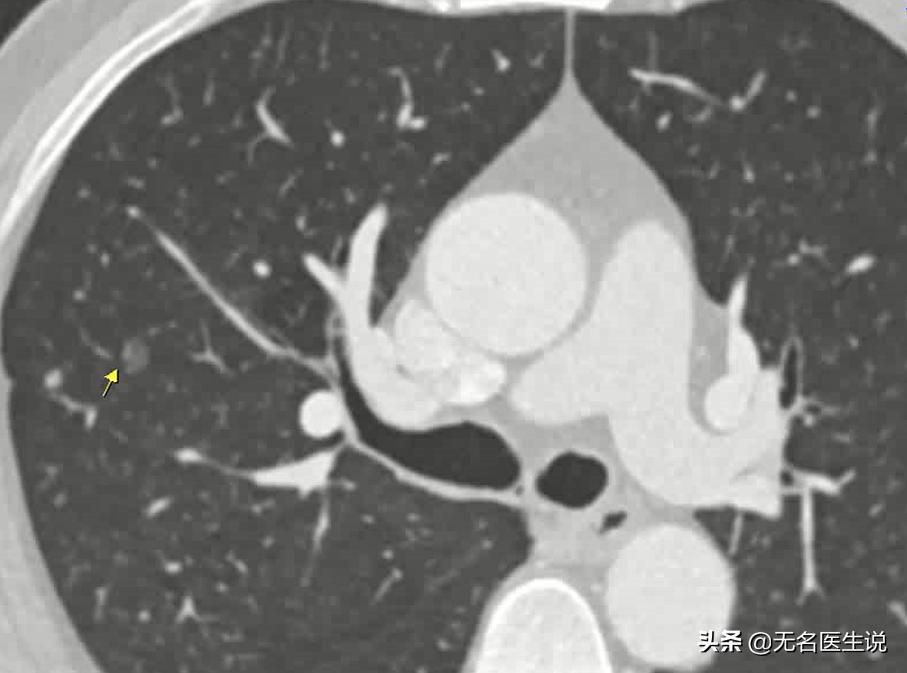

男,50岁,胸部CT发现右肺上叶前段磨玻璃结节,约0.7×0.8cm,内见扩张小血管穿过。手术治疗后病检结果为肺原位癌。

箭头所指既往磨玻璃结节,病理检查为原位癌